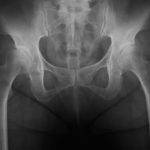

鼠径部をマッサージをすると??

はい、やってきました。   今回は、前回お話させて頂きました、鼠径部(そけいぶ)のマッサージについてのお話をさせて頂きます。   鼠径部って?と頭の中に?が浮かんだ方はコチラの記事 …

鼠径部(そけいぶ)について

みなさん、そけいぶって知ってますか?   漢字で書くと⇒鼠径部   これでそけいぶって読みます。   私もメンズエステに行くまでは、鼠径部なんて言葉知りませんでしたし、漢 …